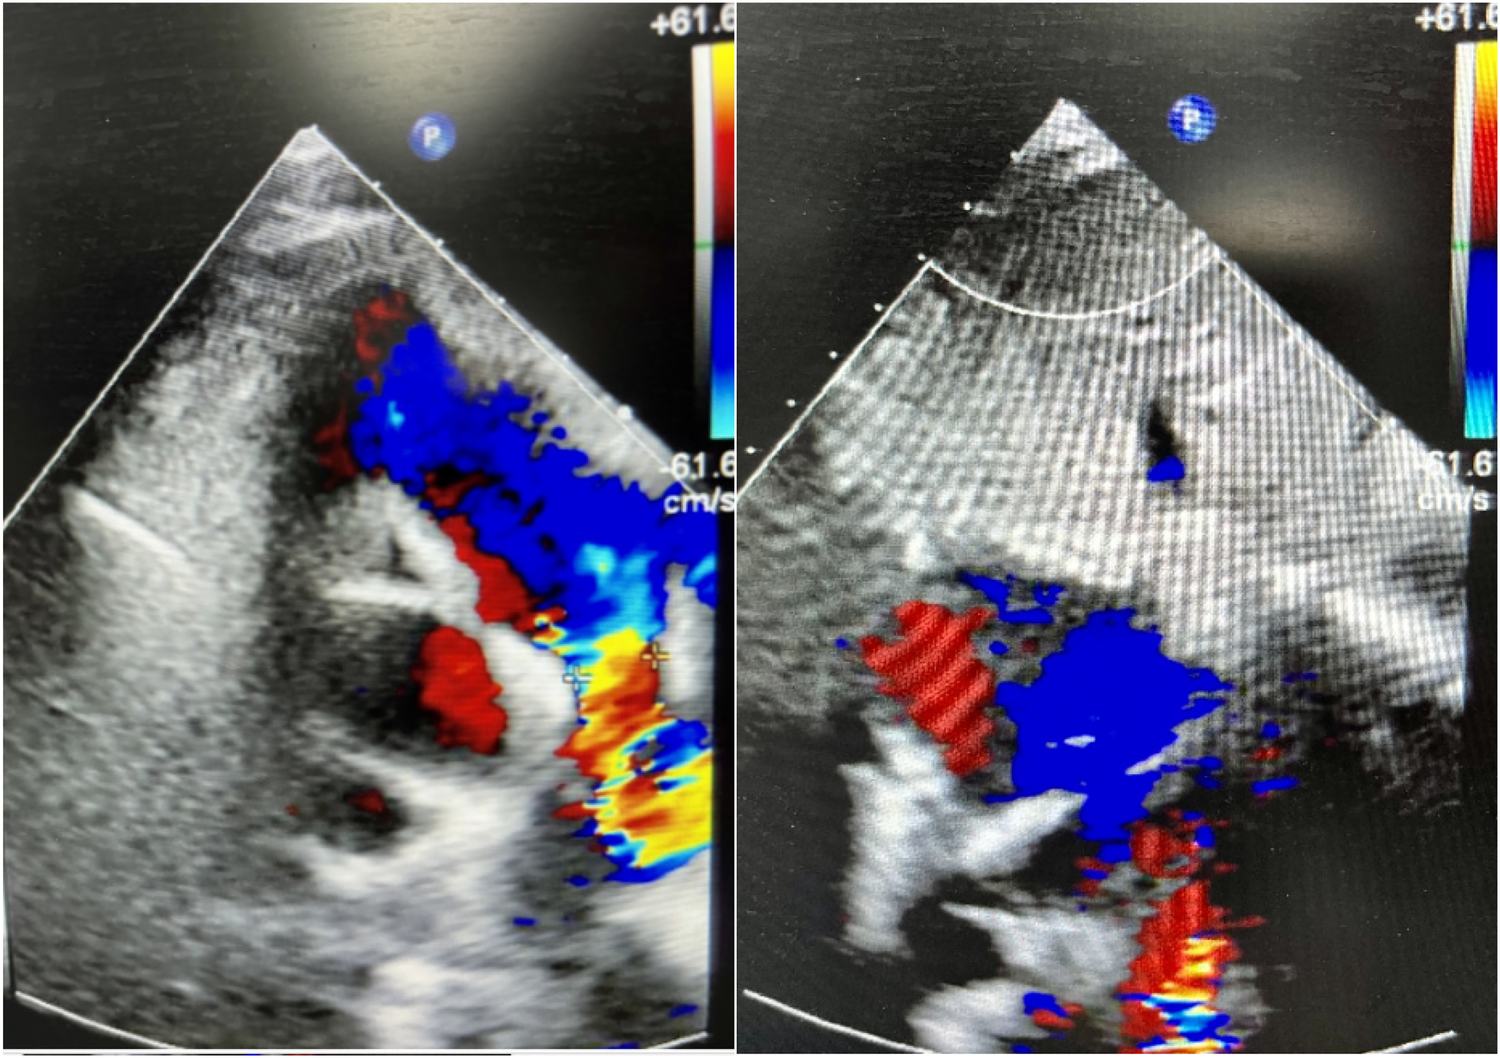

A 9-year-old female presented with a history of a cardiac murmur detected at age 1. Initial echocardiography (March 2016) revealed PDA, atrial septal defect (ASD), and PH. She reported symptoms including occasional dyspnea, reduced exercise tolerance compared to peers, post-exertional wheezing, squatting preference, cyanosis of the lips and lower extremities, and clubbing of fingers. Two prior attempts at PDA closure (May 2016 at another institution, and April 2018) were aborted due to persistently elevated pulmonary artery pressure (PAP) despite targeted therapy with endothelin receptor antagonists (ERA) and phosphodiesterase-5 (PDE5) inhibitors, initiated after the first failed attempt. Therapy evolved over time, including periods of triple therapy (ambrisentan, sildenafil, treprostinil) and dual therapy (ambrisentan + sildenafil), adjusted due to side effects and financial constraints. Upon admission to our center (January 2024) (Table 1, Figure 1, 2), physical examination revealed differential cyanosis (upper limb SpO2 90%–92%, lower limb SpO2 80%–82%), cyanotic lips, clubbing, an accentuated P2 heart sound, but no pathological murmurs. Echocardiography confirmed a large tubular PDA (10.3 mm, predominantly right-to-left shunt), secundum ASD (6.4 mm, bidirectional shunt), severe PH (estimated sPAP 97 mmHg), mild tricuspid regurgitation, and evience of right ventricular hypertrophy and dysfunction (TAPSE 11 mm, FAC 33%) (Table 2). Cardiac catheterization (March 2024) under general anesthesia confirmed precapillary PH (mPAP 57 mmHg, PCWP 9 mmHg, PVRi 11.24 WU-m2, descending aortic SpO2 77%, Qp/Qs 1.32). Following successful trial occlusion demonstrating a significant reduction in mPAP (to 45 mmHg) and normalization of descending aortic SpO2 (100%), a 20/22 mm Lifetech PDA occluder was deployed and real-time hemodynamic monitoring metrics (mPAP, PVR, SaO2). Postoperatively, triple therapy (sildenafil, ambrisentan, treprostinil) was continued. Follow-up at 3 months (June 2024) and 5 months (August 2024) post-closure showed marked clinical improvement: resolution of cyanosis (lower limb SpO2 91%–94%), improved exercise tolerance (6MWD) increased from 239 m pre-op to 333 m and then 390 m) (Table 3), and stable or slightly improved echocardiographic parameters (sPAP 100 mmHg at 3 m, 93 mmHg at 5 m; improved RV function TAPSE 19.7 mm/15.6 mm). The ASD remained patent.

Figure 2

Chest X-ray showing the lungs and ribcage. The lungs appear dark, indicating air-filled areas, while the ribs and spine are white, showing bone density. The image provides a frontal view of the thorax.

Figure 2. Chest x-ray of case 1 (January 11, 2024).